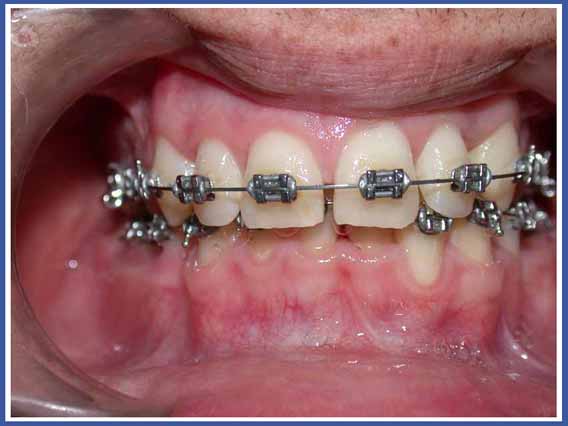

סמכים אורתודונטים (גשר) Brackets:

האמצעי הנפוץ ביותר כיום להזזת שיניים. הסמכים המודבקים לשיניים והחוט שעובר ביניהם מאפשרים להזיז את השיניים בכל שלושת המימדים בשליטה מלאה על התנועה, בניגוד לפלטות שיכולות להזיז שיניים רק בהטיה (רק לשנות את הזווית של השן בלסת). סמכים יכולים להיות מתכתיים או שקופים.

לסמכים המודבקים לשיניים יש יתרונות רבים אך יש להם גם חסרונות. החסרון העיקרי הוא הצטברות שאריות מזון וחיידקים עליהם. כדי למנוע סכנה לעששת (חורים) מסביב לסמכים, יש להקפיד על צחצוח שיניים קפדני במהלך הטיפול, ולהמנע ככל האפשר ממזון המזרז את התפתחות העששת (מזון עשיר בסוכר).